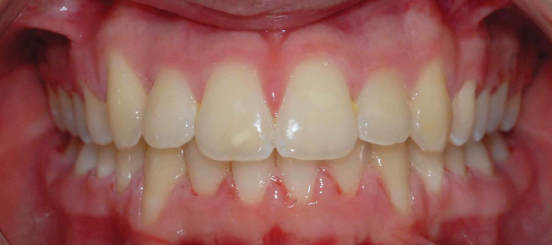

Class I Non-Extraction |